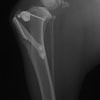

術前左後肢側面像

術前正面像

手術前後のTPA(脛骨高平部の角度)を測定しています。

約29°から約10°へ矯正されています。

術前のTPAは左後肢33.1°右後肢26.8°でしたがTPLO実施により左後肢5.5°右後肢12°に矯正されました。